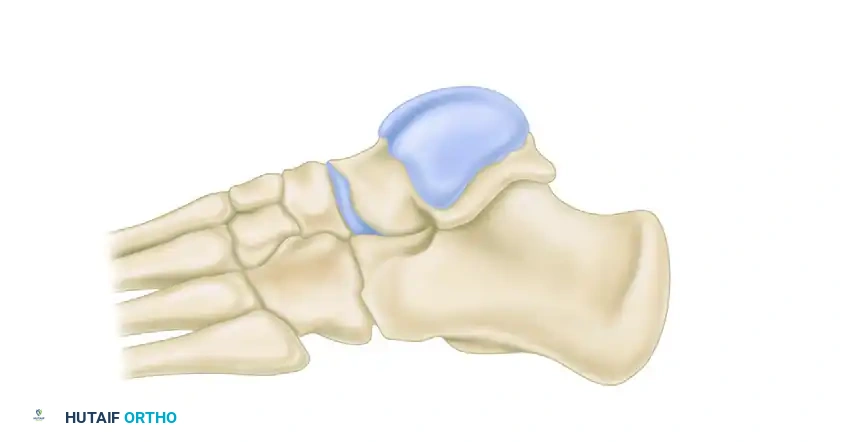

Angles of middle and posterior subtalar facets demonstrating the high variability in normal hindfoot anatomy.

Diagrammatic representation of the posterior facet orientation.

Further diagrammatic representation of the posterior facet.